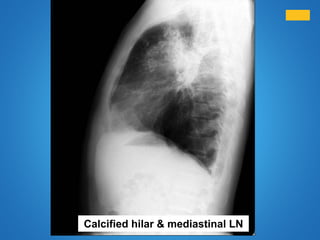

Calcified hilar & mediastinal LN